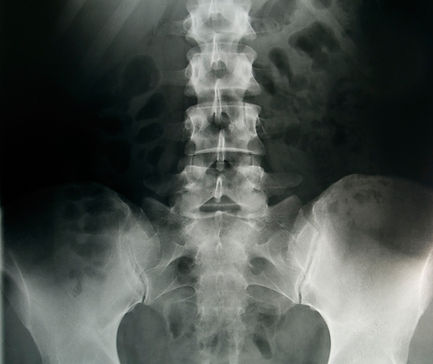

Osteoporosis-Related Spine Fractures

Osteoporosis or low bone mass is one of the most common bone diseases worldwide. Over 54 million Americans are affected with significant osteoporosis. It affects people 50 years or older significantly more frequently than the younger population.

People with osteoporosis and low bone mass are more likely to suffer from vertebral compression fractures. Please start a conversation with your primary care physician regarding prevention and treatment of Osteoporosis. This may include proper diet, exercise regimen, supplements and other medications.​

For compression fractures from osteoporosis and/or traumatic events, our providers offer percutaneous balloon kyphoplasty in many cases. These fractures are very painful in many cases and can cause significant morbidity.

While conservative treatment may be indicated in some cases, there is increased evidence that kyphoplasty procedures can reduce morbidity and pain associated with these fractures significantly. This can result in resuming activities earlier in many cases.​​